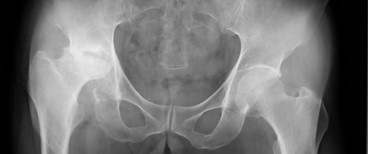

発症から現在まで &レントゲン・MRI お気楽ではない レントゲン・MRI  2007年10月 クリックすると拡大して見れます。(別画面でひらきます) 2008年3月 2009年1月のレントゲンはここから骨棘(こつきょく)の状態が確認できます。 2012年4月のレントゲンはここから骨嚢胞(こつのうほう)が確認できます。 MRIはこちらから  発症から現在まで 2008年末まで 2011年末まで(表示中) 2009年末まで 2017年末まで 2010年末まで 2025年末まで

2011年は3月11日に東日本大震 災もあったし、桜の開花も遅く、梅雨 もかなり短かかったり、季節の移り変 わりもどこかおかしくなっているよう に感じます。 年明け早々の1月19日、病院で撮っ たレントゲン、毎回「大きな変化は無 い」と言われてたんです。でも、たま たまなんですが、骨頭が大きく潰れた 2008年3月の写真と比べて診ても らいました。結果は骨頭が更に5ミリ くらい削れていたことが分かりました。 ある時急に削れたのか、3年かかって 少しずつ削れたのかは分かりません。 ちょっとショックでした。 冬の寒さ対策ではショートのレッグウ ォーマーで十分でした。 ですが、2月半ば頃から3月上旬にか けては股関節と右の膝が暫くシクシク としました。やっぱりそれなりに寒さ の影響があったのでしょう。 4月からは、それまで日曜日以外の定 例的な休みは火曜日だったんですが、 それが月曜日に変わりました。毎週5 日間の連続出勤をするようになって、 右膝に痛みが出易くなってしまいまし た。歩くのが辛くなるくらいの痛みで す。多分これからの大きな課題になる と思います。 3年近く続けた加圧トレーニングは昨 年末で中断することになり、代わりに 1月18日からスポーツジムで筋トレ を始めました。基本火曜日、木曜日、 土曜日の週3回です。 メニューは3月になってやっと定型的 なものができましたが、その内容はま た別途報告したいと思います。 それから4月下旬にトレーニングのや り過ぎで右膝を痛めてしまいました。 それからは膝に負担のかかる運動は控 えるようにしています。 |